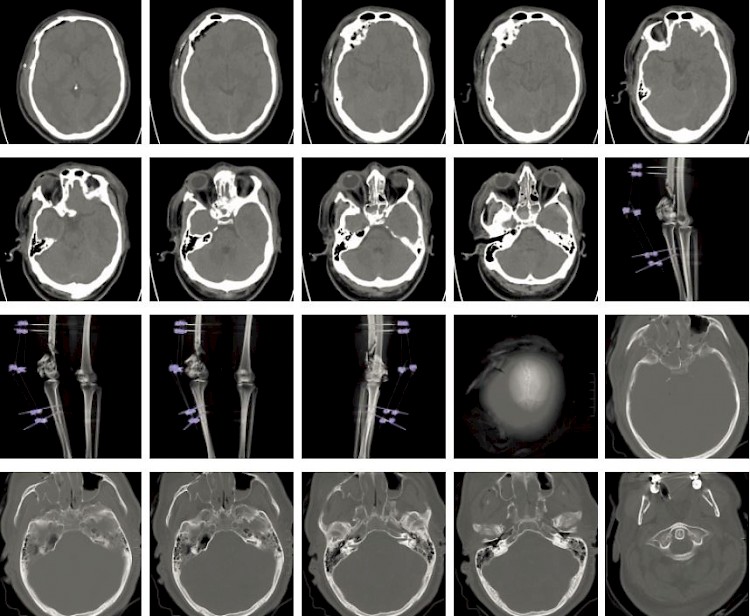

Fallbeispiel

Schädel-Hirn-Trauma nach Verkehrsunfall

Ein Autofahrer war auf der BAB unterwegs, bis er von der Fahrbahn abkam. Er wurde mit dem RTW in das nächste Krankenhaus gebracht, wo er dann als Polytrauma-Patient im Schockraum behandelt wurde.

Primär wurde eine Beckenübersichtsaufnahme und ein Rö-Thorax angefertigt. Nach der Erstversorgung wurde der Mann ins CT gebracht, wo dann das Traumascan gefahren wurde

Nachstehend einige Bilder des Traumascans.

Befund:

- Schmales subdurales Hämatom Li temporal und re frontal.

- Deutliche Hirnschwellung.

- Ausgedhnte Gesichtsverletzung mit Beteilung der Frontobasis und der Schädelkalotte re frontal.

- Fraktur der mitteleren Schädelbasis und des Felsenbeins li.

Thorax und Abdomen waren fast ohne Befund, nur die Lunge erlitt Kontusionen. Was aber nicht ungewöhnlich bei einem Hochrasanztrauma ist. Zudem hatte der Patient multiple Frakturen an beiden Beinen.